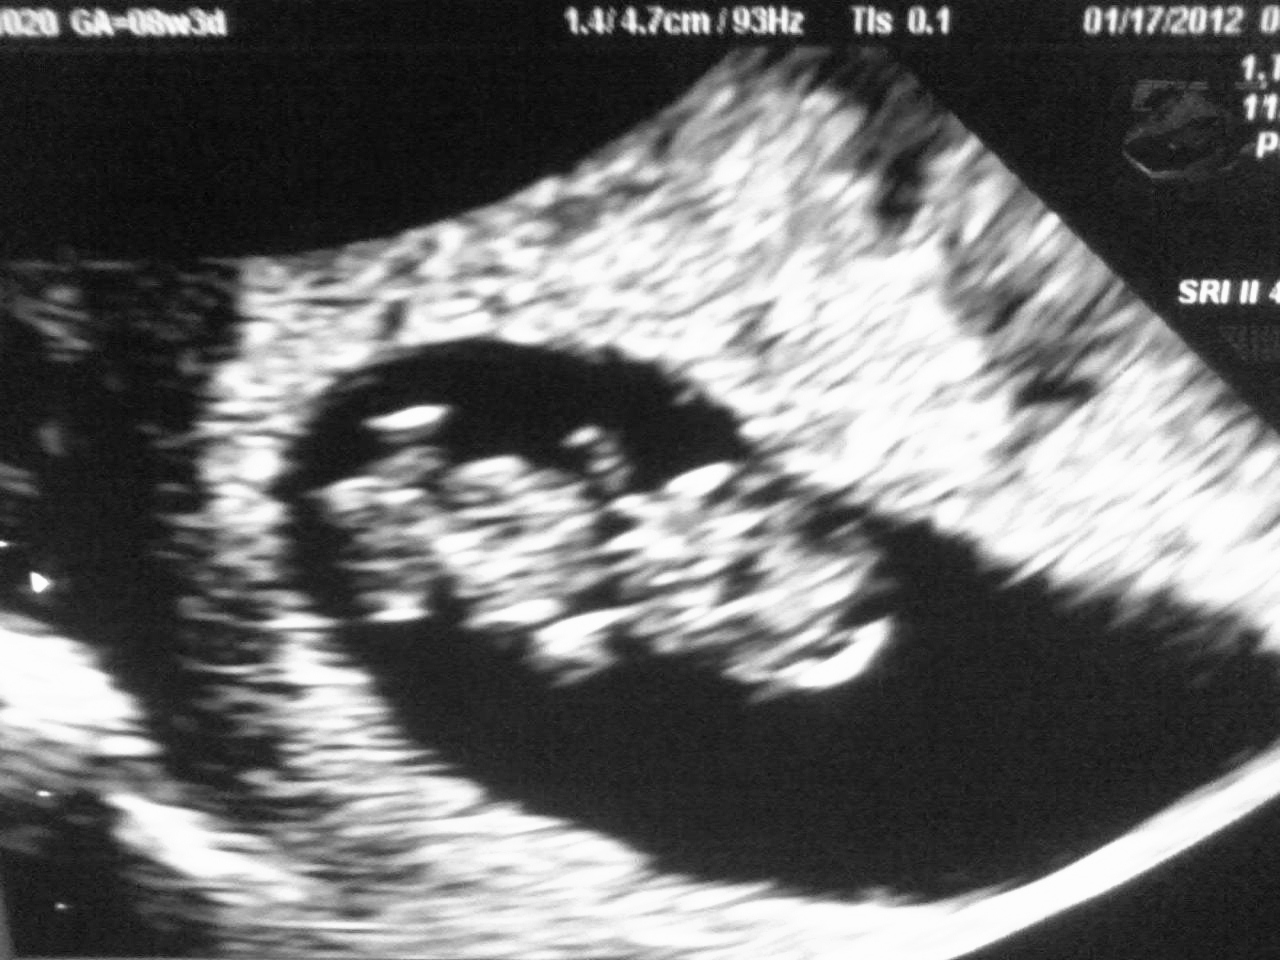

Two weeks from today we go for our second appointment at the doctor for the baby. I can't wait. The appointment after that we will be able to hear the heartbeat.